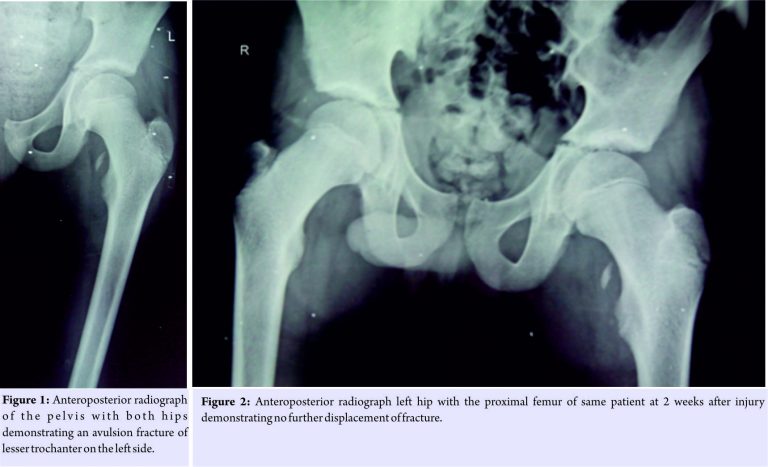

Between 2014 and 2016, three patients of isolated avulsion fractures of lesser trochanter presented to our hospital (Table 1). All three were adolescent males, two were aged 13 years old, and one was 15 years old. Two patients had involvement of left side while running in a school sprinting competition and were unable to complete race while hearing a sudden pop at the time of injury. The other had right side involvement and sustained trauma due to fall from horse. All patients reported immediately to hospital with complaints of pain in groin, limp, and antalgic gait on presentation. General physical examination was unremarkable. There were no swelling or visible external signs of trauma in any patient. Local examination in supine position was done. Attitude of the limb revealed slight flexion and external rotation deformity. No patient could do active straight leg raise. There was tenderness around the groin and medial aspect of the upper thigh. Flexion of hip was painful, and rotations inflexion were more painful than an extension of hip. Distal neurovascular status of the limb was normal in all cases. There were no significant associated injuries in any patient. Radiographs of the pelvis with both hips revealed avulsion fractures of lesser trochanter (Fig. 1). All fractures were displaced <1.5 cm on radiographs. We did not go for further imaging studies as both the diagnosis and displacement were evident on radiographs. All patients were managed conservatively including analgesics and non-weight bearing mobilization with crutches for 2 weeks followed by partial weight bearing as tolerated. Repeat radiographs at 2 weeks revealed no further displacement of the fragment in any patient (Fig. 2). Passive mobilization of hip and muscle strengthening exercises were started once patients were pain-free after 3 weeks. All patients could bear full weight at 6 weeks. At 12 weeks, no patient had any complaint, had resumed activities of daily living, and hip flexion strength was comparable to opposite side.